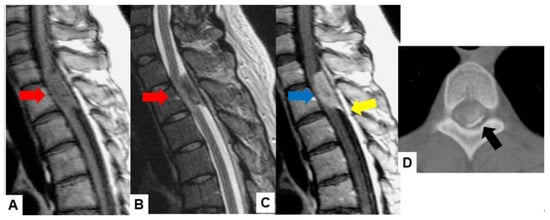

Meningiomas usually indicate isointensity in both T1- and T2-weighted MR imaging and are enhanced homogeneously (Figure 3) [35]. Meningiomas are sometimes calcified and are recognized in CT (Figure 4). The key points of a differential diagnosis of meningioma and schwannoma are in Table 4.

Figure 3.

Forty-two F, spinal meningioma. (A) T1-weighted midsagittal image, (B) T2-weighted midsagittal image, and (C) enhanced T1-weighted midsagittal image. (D) CT. Red arrows indicate tumor and blue arrow shows tumor enhancement. Yellow arrow shows dural tail sign and black arrow indicates tumor ossification.

Figure 4.

Sixty-eight F, spinal meningioma. (A) Enhanced T1-weighted midsagittal image, (B) enhanced T1-weighted axial image at T7/8, (C) T2-weighted midsagittal image, (D) T2-weighted axial image at T7/8, (E) midsagittal reconstruction CT, and (F) axial CT at T7/8. Red arrows indicate tumor, and blue arrows show tumor enhancement. The tumor is calcified (white arrows).